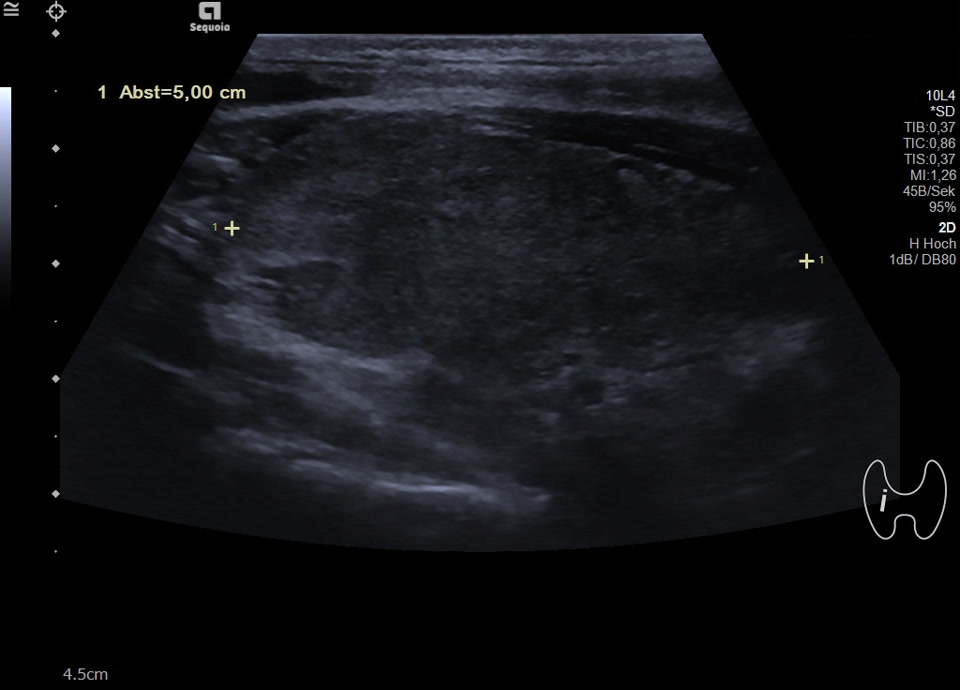

36-jähriger Patient mit Tremor, Tachykardie, Exophthalmus und Gewichtsverlust. Sonographisch stellt sich die Schilddrüse beidseits mit echoarmer inhomogener Parenchymstruktur dar. Gesamtvolumen 20,5 ml. Farbdopplersonographisch hypervaskularisiert. Laborbefunde: basales TSH erniedrigt, T3/fT4 erhöht, TRAK positiv. Befundkonstellation vereinbar mit M. Basedow. Unter Therapie mit Thiamazol und Propranolol beschwerdefrei. Bei Verlaufskontrolle zwei Jahre später sonographisch echoreiches minimal inhomogenes Parenchym bei normalem Volumen (15 ml).